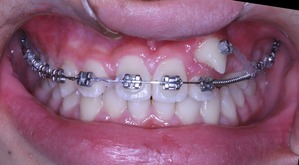

現在の状況はもう少し治療が進んでいるのですが、矯正歯科ネットユーザー様からの質問が昨日でしたので、数か月前の記録ですが、現在の進行状況です

正面と側面の写真をみてもあまり変化がわからないと思います。

上からみてみるとどうでしょうか?

もう少し犬歯が後方に移動してもらえると、2番目の歯が前方に移動可能な感じです